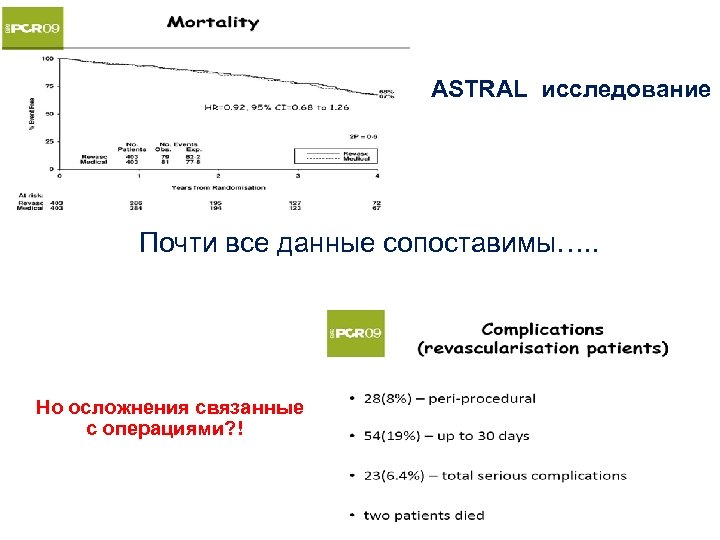

ASTRAL исследование Почти все данные сопоставимы…. . Но осложнения связанные с операциями? !

ASTRAL исследование Почти все данные сопоставимы…. . Но осложнения связанные с операциями? !